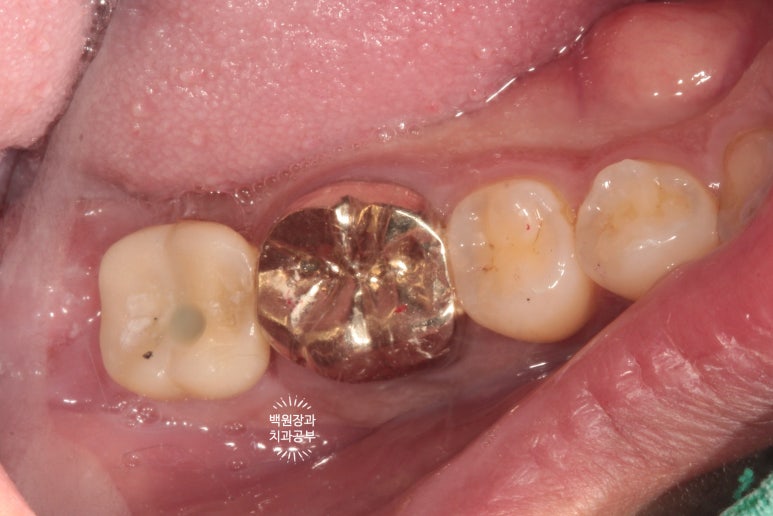

수술 후 약 3개월 정도 지난 후의 입 안 사진입니다.

다소 잇몸에 수술 자국은 있어보이나, 대체로 잘 아물어 있는 것을 볼 수 있었습니다.

다시 한 번 간단한 시술을 통해 임플란트 주변 뼈이식이 잘 유지되고 있는지를 확인합니다.

덴티움 뼈이식재와 차폐막은 오랫동안 형태를 유지하며 조화로운 치료 결과를 보여주네요.

아주 만족스러운 결과를 직접 눈으로 확인하고 치유지대주 (Healing abutment)를 연결해드렸습니다.

잘 보시면, 처음에 치료된 모습 그대로 잘 유지되고 있는 임플란트 크라운을 왼쪽에서 보실 수 있습니다.

충분히 단단한 지르코니아 크라운으로 제작된 임플란트는 오랜 수명을 자랑합니다!

그리고 오른쪽 사진에서, 아주 완벽하게 잘 유지되고 주변 잇몸과 조화로움을 자랑하는 임플란트를 보실 수 있을거에요. 얼핏 보면 자기 치아랑 헷갈릴 정도라니깐요..

오스템임플란트와 덴티움 뼈이식재 조합이 아주 좋은 결과를 보여주었네요.